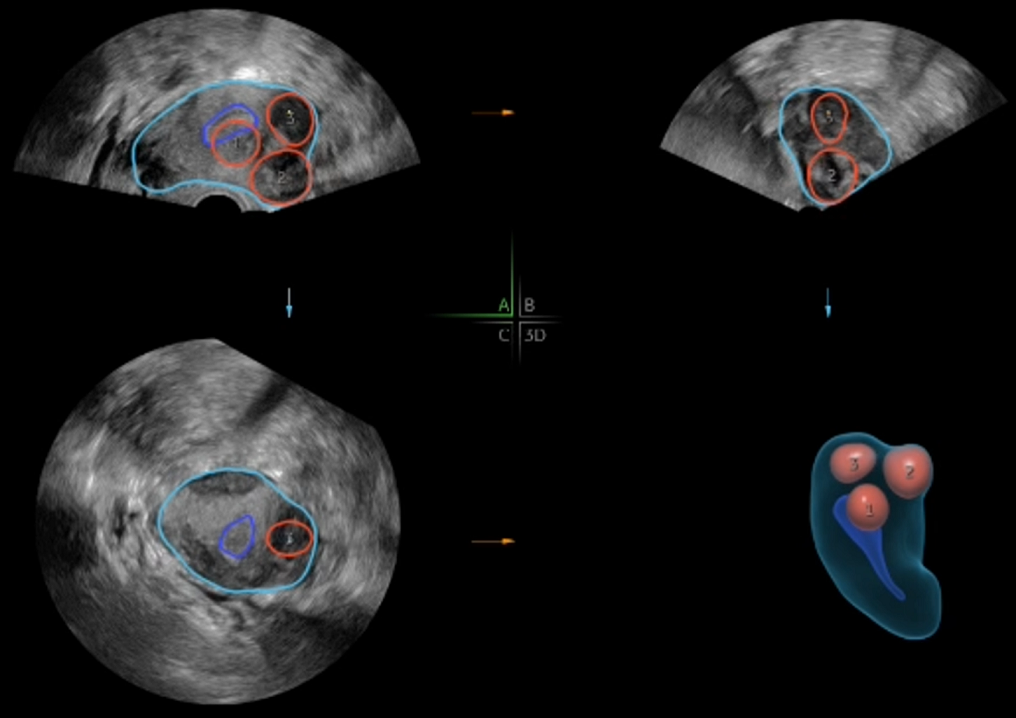

6. Otomatik Folikül Takibi (S-AVC)

7. Uterin anomaliler, polip, myom gibi patolojilerin tanımlanması

AI destekli 3D boyutlu ultrasonografi cihazları sayesinde uterusa ait doğuştan gelen ya da sonradan kazanılmış anomalilerin tanımlanması ve bu patolojilerin rahim içerisine olan etkisi kolaylıkla daha ileri görüntüleme yöntemleri kullanılmadan inceleme yapılmaktadır.

Embriyoloji laboratuvarımızda, yapay zekâ destekli sistemler sayesinde embriyo ve yumurta hücreleri (oosit) değerlendirilmekte, en uygun sperm seçimi yapılmaktadır. Kliniğimizde ise 3D ve yapay zekâ destekli ultrason cihazları ile folikül takibinin yanı sıra miyom, polip ve uterin anomalileri de yüksek hassasiyetle tanımlanmaktadır.